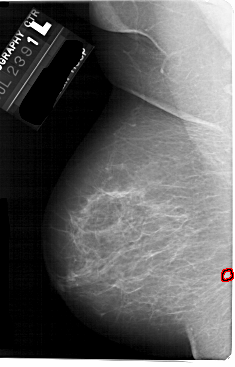

A_1738_1.LEFT_MLO

LEFT_MLO LINES 5491 PIXELS_PER_LINE 3511 BITS_PER_PIXEL 12 RESOLUTION 43.5 OVERLAY

FILE: A_1738_1.LEFT_MLO.OVERLAY

TOTAL_ABNORMALITIES 1

ABNORMALITY 1

LESION_TYPE MASS SHAPE LOBULATED MARGINS ILL_DEFINED

ASSESSMENT 4

SUBTLETY 2

PATHOLOGY BENIGN

TOTAL_OUTLINES 1

BOUNDARY